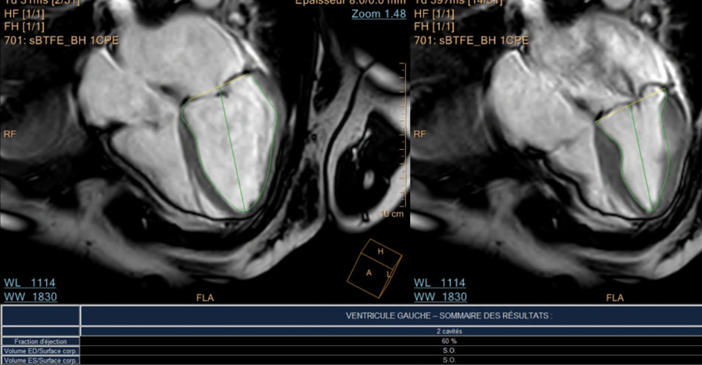

A cardiac MRI was performed, finding a preserved left ventricular ejection fraction with infero-septal hypoperfusion without evidence of necrosis in the viability sequences; high-grade mitral regurgitation is confirmed; no abnormality suggestive of myocarditis were found.